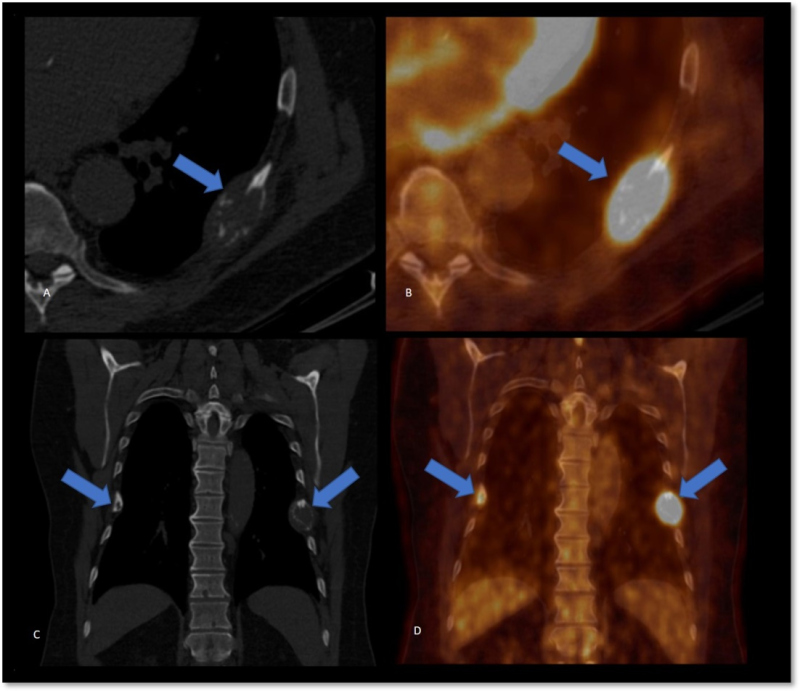

A raíz del hallazgo tomográfico y por sospecha de patología oncológica se solicita PET- CT con fluorodesoxiglucosa (18F-FDG), donde se advierten múltiples lesiones óseas líticas hipermetabólicas (algunas con erosión de la cortical), incluyendo un foco esternal con SUV máx. 8,4, otra en el 7° arco costal derecho (fig. 1) y una tercera imagen focal con insuflación cortical, densidad en vidrio esmerilado en su interior ubicada en tercio medio femoral (fig. 2, arriba), con algunos otros focos hipermetabólicos sin traducción tomográfica. También se evidencia a nivel submaxilar derecho una lesión con densidad de partes blandas, con captación aumentada (SUV máx. 4,2) y centro fotopénico en relación a necrosis.